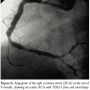

Case Report. A forty-year-old, male, chronic smoker, non-hypertensive, and non-diabetic patient presented to us with Canadian Cardiological Society class III angina of 1-month duration following an acute inferior wall myocardial infarction (MI) for which he was not thrombolyzed (having presented beyond the window period). Echocardiogram showed severe hypokinesia of the inferior wall with normal contractility of all the other myocardial segments and a global left ventricular ejection fraction of 50%. The patient was taken up electively for coronary angiogram and possible myocardial revascularization. Prior to angiogram, the patient was given a loading dose of clopidogrel and aspirin. Angiogram of the left system revealed an ectatic left anterior descending artery (LAD) with TIMI-3 flow, a normal left circumflex artery (LCX) and retrograde filling of the posterior descending artery (PDA) and posterior left ventricular (PLV) branches of the RCA from the left system. Angiogram of the right system showed total occlusion of the proximal RCA (Figure 1). After giving a bolus of abciximab (0.25 mg/kg body weight bolus

followed by infusion of 0.125 µg/min for 12 hours), the patient underwent percutaneous transluminal coronary angioplasty (PTCA) of the RCA. The RCA was engaged with a 7 Fr Judkins right guiding catheter (Boston Scientific, Natick, Massachusetts) and the lesion was profiled in various views. The lesion was crossed with a Balance Middle Weight (BMW) Universal™ guidewire (Guidant Corporation, Temecula California) and dilated with a 2.5 x 10 mm Amadeus balloon (Eurocor, Bonn, Germany). Postdilatation injection revealed a large ectatic RCA loaded with thrombus extending from the ostium to the distal vessel with no significant stenosis (except for nonvisualization of the PLV) and TIMI-1 flow (Figure 2). In view of the large thrombus burden, an X-sizer thrombectomy/thrombosuction device (Model No. XS-CS 1200-60; EndiCOR Medical Inc., San Clemente, California) with a cutting diameter of 2.0 mm was passed up to the distal RCA and thrombosuction was done from distal to proximal RCA. Post-thrombosuction angiogram, however, revealed no appreciable change in the thrombus burden. Therefore, a 3 Fr Tracker perfusion catheter with side holes (Target Therapeutics, Fremont, California) was passed over the guidewire up to the distal RCA, over which a 7 Fr right coronary guiding catheter was